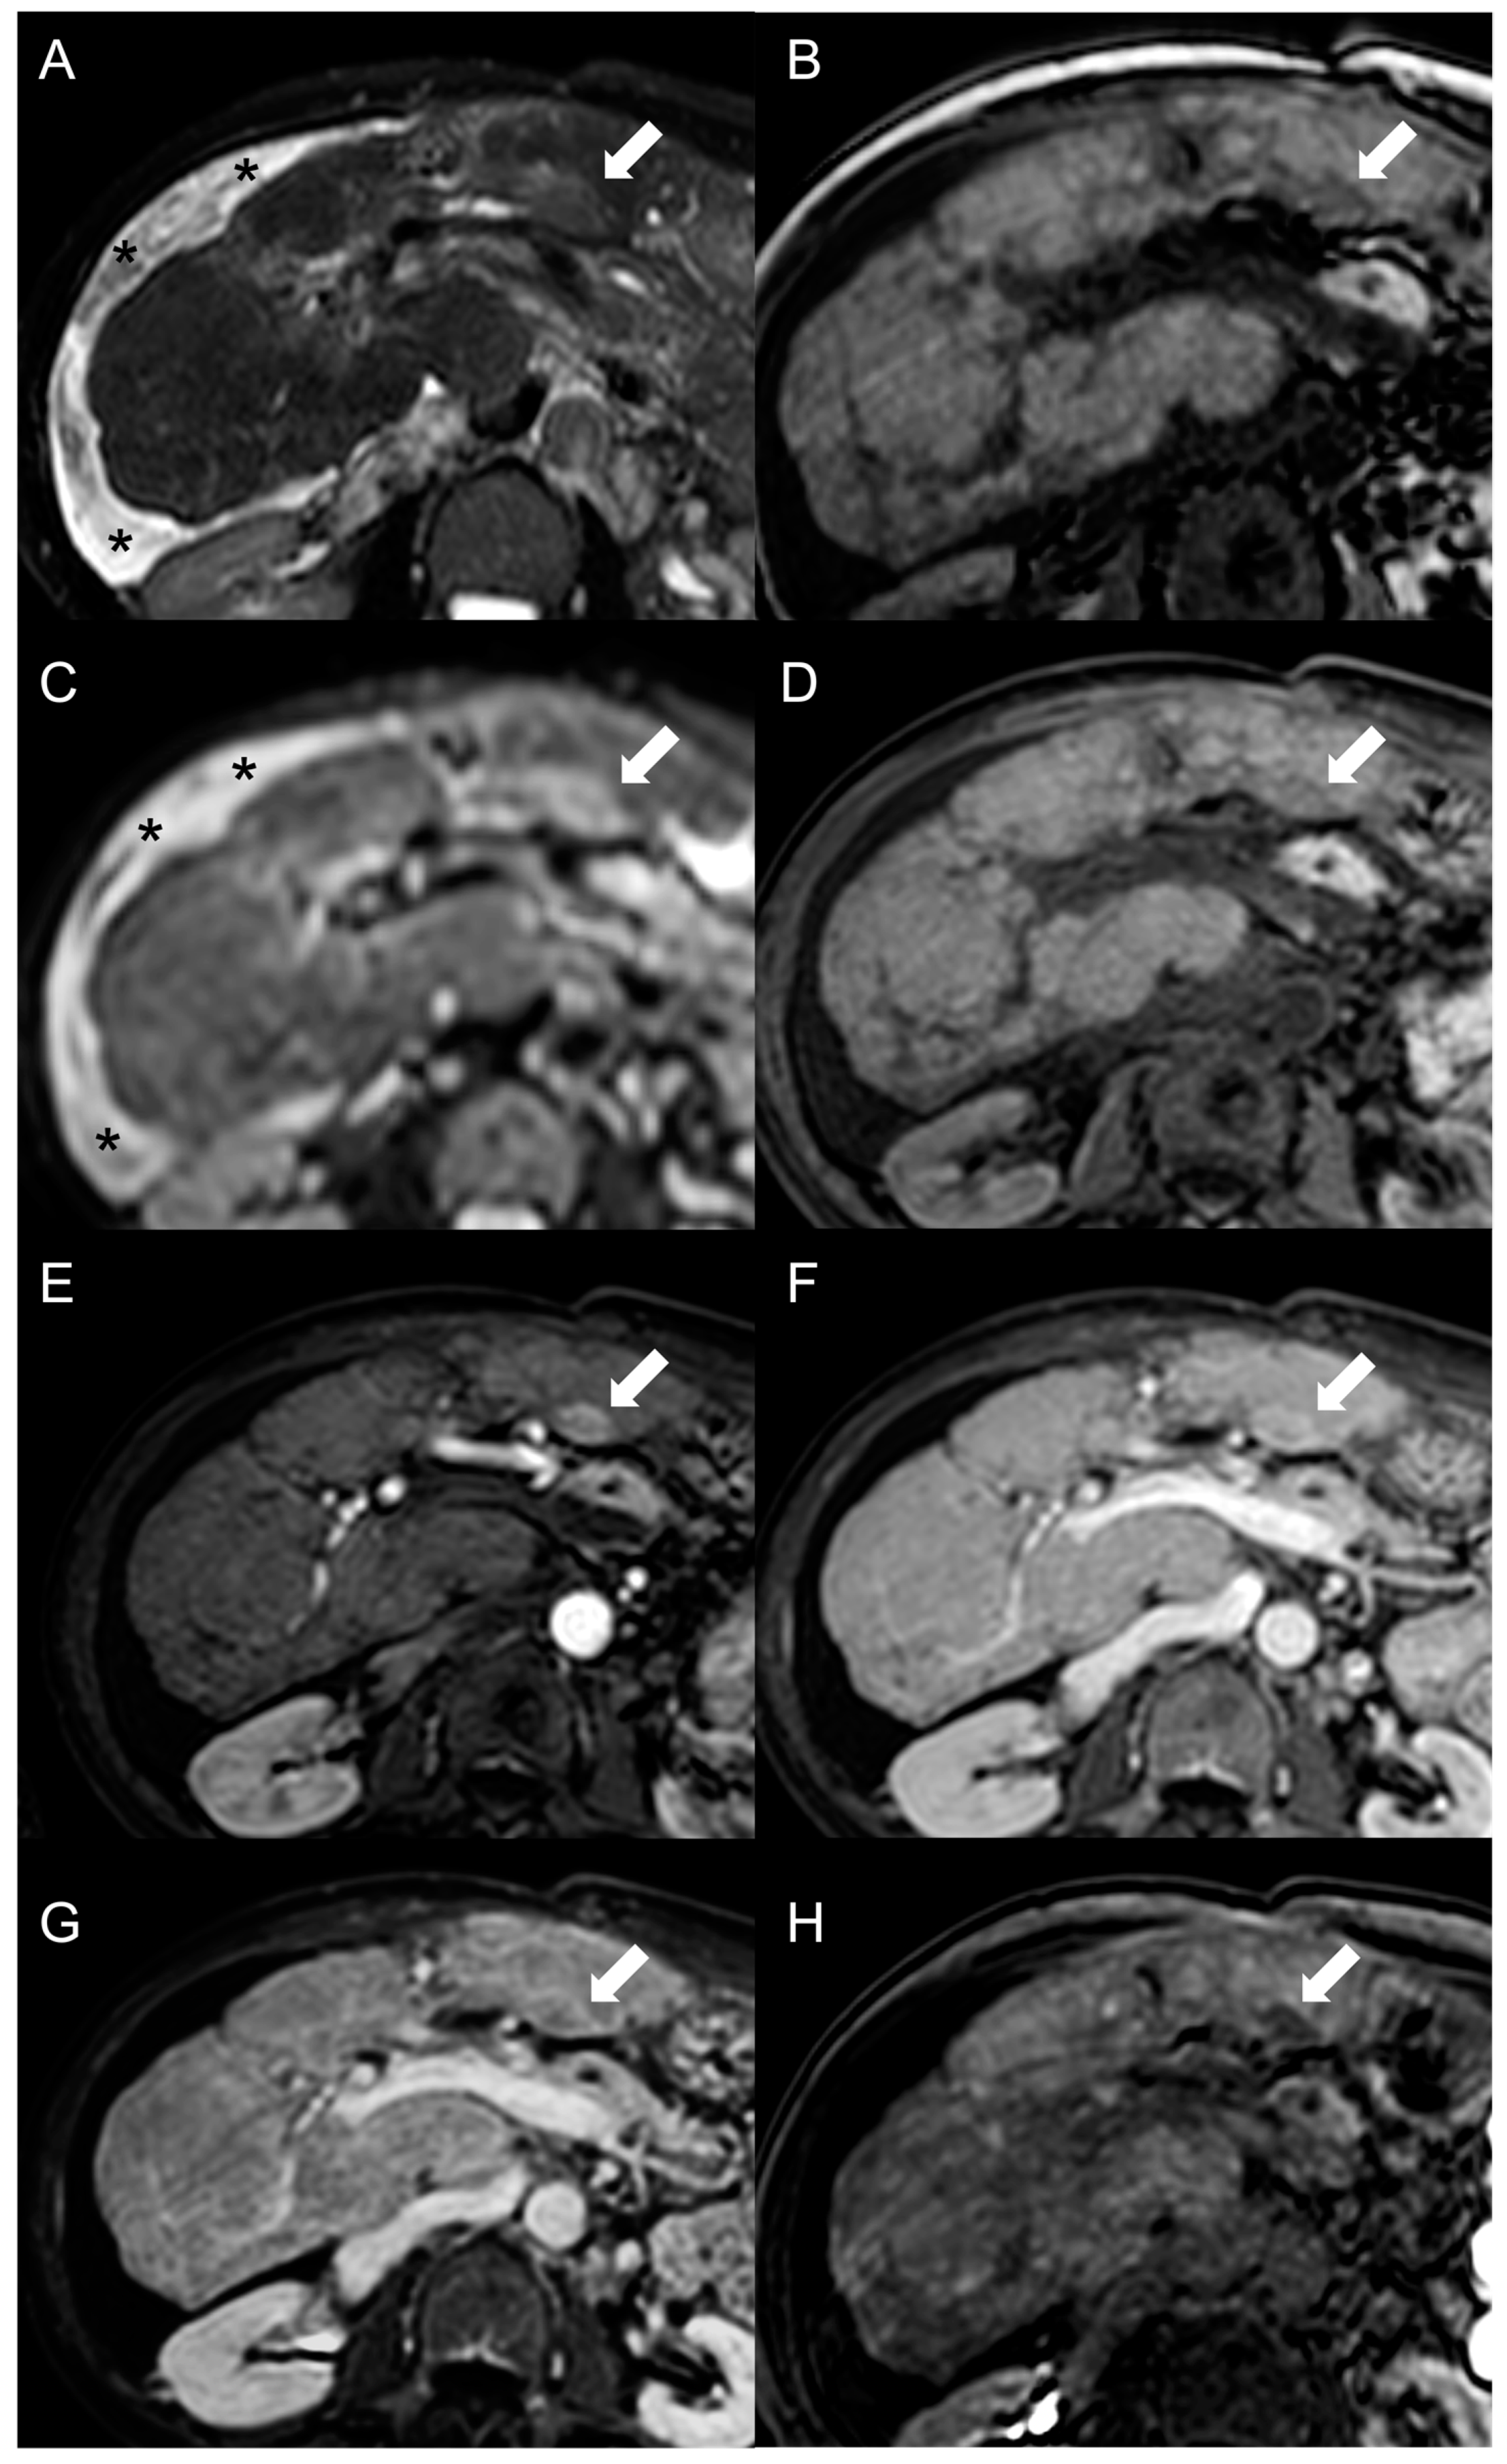

MRI features of FNH-like RNs are shown in Figure 3.

Figure 3.

MRI examination of a 29-year-old female with Budd–Chiari syndrome. On fat-saturated T2-weighted images (A) FNH-like RNs are barely discernable as they appear isointense to the liver parenchyma; occasionally, areas of very slightly hyperintense signal (arrow) can be identified, possibly related to congested nodules or central scar. On out-of-phase T1-weighted images (B) the presence of nodular lesions is more appreciable, as FNH-like RNs (arrow) appear slightly hyperintense compared to the surrounding liver parenchyma. On DWI (b-value = 600) (C), FNH-like RNs may show a slight heterogeneous hyperintensity due to central scar or congestion. On unenhanced gradient-echo T1-weighted images (D), the nodules (arrows) appear hyperintense, while on arterial phase (E) they show vivid enhancement with a peripheral hypointense rim due to hepatic tissue congestion. On portal venous (F) and delayed (G) phases, the nodules become progressively isointense to the liver. On the T1-weighted images (flip angle = 30°) in the hepatobiliary phase (H), FNH-like RNs show hyperintensity compared to the surrounding liver parenchyma.

Besides changes in size, as mentioned above, the MRI features of FNH-like RNs can alter during the follow-up period (Figure 4). For example, the T1 and T2 signal intensity may change, more frequently with a shift from hyperintense to isointense on T1-weighted images and from hypointense to isointense on T2-weighted images. The enhancement pattern may vary as well, with washout acquired in 8% of cases and lost in nearly 20% of cases.

Figure 4.

MRI examinations of a 31-year-old male patient with Budd-Chiari syndrome performed in 2016 (A), 2017 (B), 2018 (C), and 2020 (D). Gradient-echo T1-weighted sequences (flip angle = 30°) acquired in the hepatobiliary phase revealed a 25 mm FNH-like RN (arrows) with central scar and peripheral hyperintensity in 2016 (A). The lesion size grew to 41 mm after 1 year (B) and further to 44 mm after 2 years (C), but it reduced to 35 mm in 2020 (D). Additionally, new FNH-like RNs appeared over time (arrowheads in C,D).